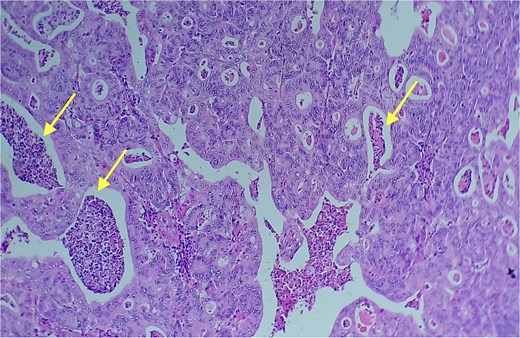

Red and white pulp of the splenic parenchyma (arrow) with infiltration by intestinal-type adenocarcinoma (double arrow, left); H&E ×200.

Area of enteric-type adenocarcinoma composed of neoplastic proliferation of columnar epithelial cells with nuclear atypia, eosinophilic cytoplasm, and a complex tubular and cribriform arrangement with endoluminal necrosis (arrows); H&E ×200.